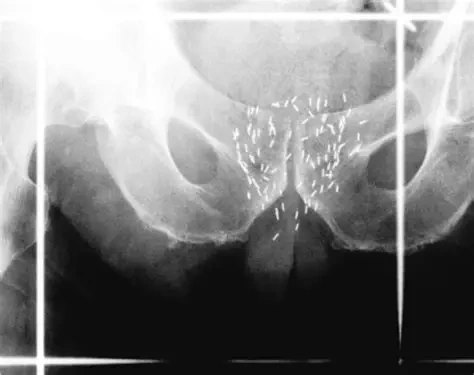

비뇨의학과 역시도 방사능을 많이 다루는 수술과 중에 하나다. 요로 결석 수술이라든가 또한 전립선암 수술 시 브래키치료(brachytherapy)라고 하여 방사능 동위원소 칩을 전립선암 주위에 삽입하는 수술 등이 있다. 전립선암에 대한 브래키치료 방법은 방사능이 나오는 것을 이용하여 전립선암을 제거하는데 이용한다.

OIP.YgCB6PoGH3_dla4qrFW8fwHaF3?rs=1&pid=ImgDetMain&o=7&rm=3 전립선암 주변에 방사능 칩을 삽입한다.